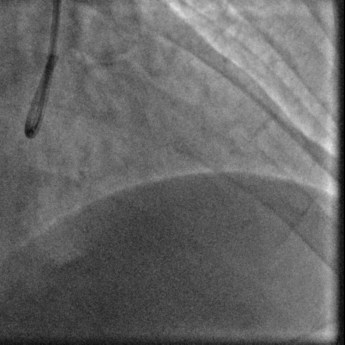

冠脉造影:

蜘蛛位

左头